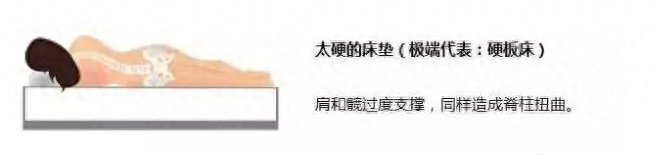

5. 睡软硬适中的床

睡硬板床时,人体的重力集中在头、肩、臀、脚处,硬板床在过度支撑肩部和臀部的同时,腰部却处于无支撑的悬空状态,导致脊柱扭曲。

所以,硬板床无法保持腰椎的正常生理曲度,有可能加重肌肉僵硬和腰突症状。

当床过软时,在腰臀重量的压力下,形成了腰臀部下陷、头部腿部两边高的体位。使得脊柱无法得到适当的支撑,腰部肌肉一直处于拉伸状态,无法得到充分的休息。所以,过软的床不适合腰椎间盘突出患者。

而软硬适中的床能让人保持自然体位,脊柱的扭曲度最小,最适合腰椎间盘突出患者。